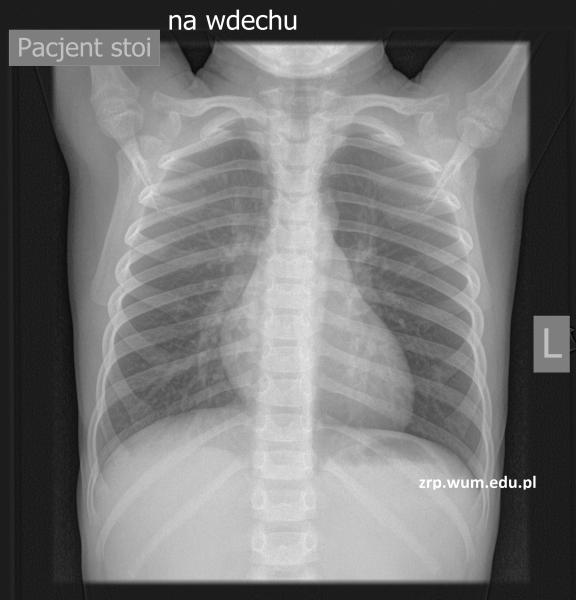

Przypadek 13: 4-letni pacjent z podejrzeniem aspiracji ciała obcego do dróg oddechowych, stan po zakrztuszeniu się marchewką.

Rozpoznanie: W badaniu RTG klatki piersiowej wykonanym standardowo, na wdechu - bez zmian, cieniującego ciała obcego nie uwidoczniono. Dodatkowe zdjęcie wykonane na wydechu uwidoczniło masywne rozdęcie lewego płuca z przemieszczeniem śródpiersia na stronę prawą - cechy RTG pułapki powietrznej, pośredni objaw obecności ciała obcego powodującego niedrożność lewego oskrzela. Pacjent skierowany na bronchoskopię.